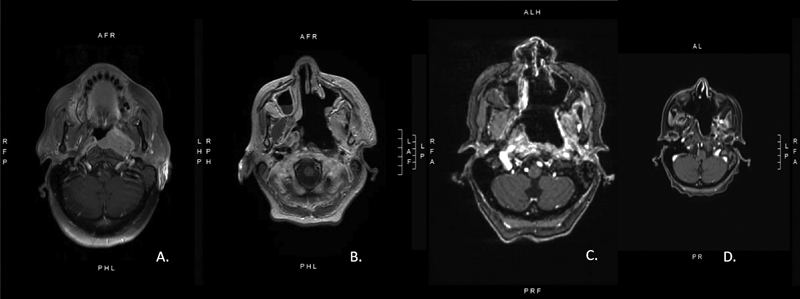

Nasopharyngeal Carcinoma: Case Presentation and Literature Review of Treatment Innovation with Immunotherapy.

Nasopharyngeal carcinoma (NPC), a rare head and neck malignancy, arises from the epithelial lining of nasopharyngeal mucosa. The confluence of various risk factors, such as latent Epstein-Barr virus infection, genetic susceptibility, smoking, alcohol consumption, and high nitrosamine diet, is thought to contribute to NPC pathogenesis. Radiation therapy serves as the mainstay of treatment for early stage while concurrent chemotherapy and radiation are the basis of treatment for locoregional advanced disease with overall 80% five-year survival rate. Recurrent or metastatic disease pose treatment challenges as reirradiation, repeat cycles of chemotherapy, and surgery follow with high likelihood of treatment toxicity or postoperative morbidities. Typically reserved for nonresectable recurrent or metastatic disease, immunotherapy serves as novel treatment for NPC. NPC tumor microenvironment predominated by a dense infiltrate of immune cells hosts an ideal target for immunotherapy. Several clinical trials have investigated the efficacy of anti-programmed cell death protein 1 antibodies such as pembrolizumab, nivolumab, and camrelizumab with promising results. Treatment of recurrent and metastatic NPC remains a challenge; however, the advent of immunotherapy has provided additional options and potential for preventative and therapeutic measures.